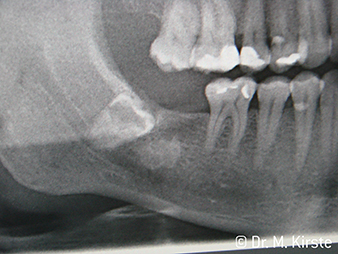

W&H Ejemplo de un paciente

Figura 6: Ejemplo de un paciente: El diente desplazado 48...

Figura 7: ...se extrae fácilmente con el nuevo contra-ángulo.